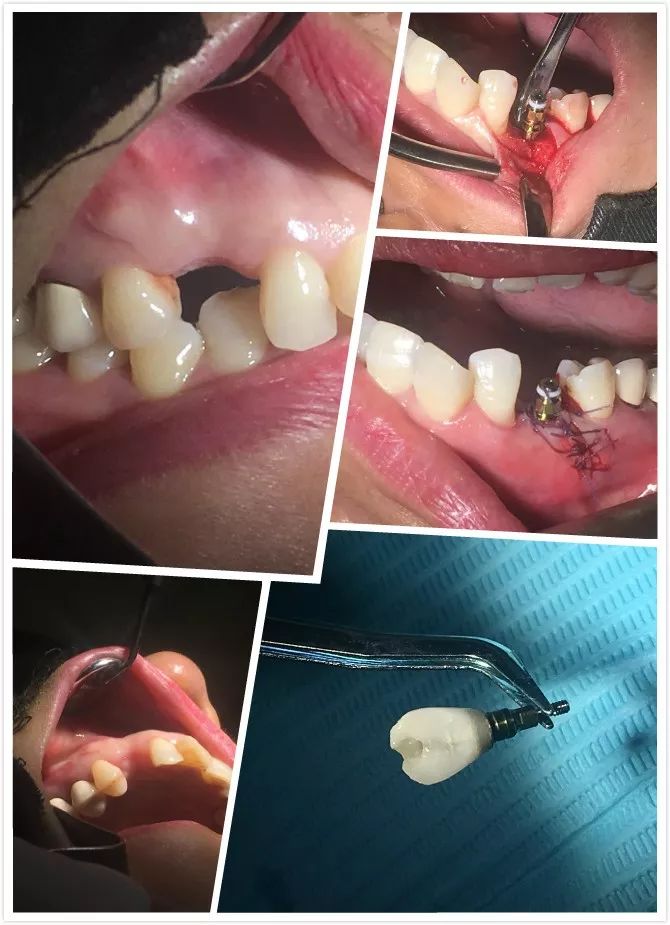

1 讲师简介 梁光强老师 (毕业于首都医科大学) 2 课程安排 第一天 1、口腔种植的基本概念 2、口腔门诊开展简单种植应该了解的基础知识 3、拓展种植牙业务医患交流技巧 4、民营口腔如何开展种植牙项目 5、开展种植所需要的设备,耗材以及所需要的准备工作 6、种植体的表面处理 7、如何读懂X光片 8、种植术前的评估--步骤与方法 9、缝合原则 10、{实习操作}缝合练习,种植X片的现场评估 第二天 1、种植牙手术术前准备 2、种植牙术中,术后的注意事项 3、种植手术植入流程 4、修复方式选择 5、印模技术 6、种植二期上部结构修复 7、门诊观看种植牙手术 8、{实习操作}种植植入模型实际操作 第三天 1、种植牙修复的并发症及处理方式 2、简单上颌窦提升技术 3、即刻种植 4、{实习操作}种植修复二期取模实际操作 3 病例展示 病例一 4 招生信息 主题:《走进民营-快速开展种植牙》 时间:2022年3月8日—3月10日 地点:宗言公司 主讲:梁光强老师 费用:老学员3600元/人(不含税)新学员3800元/人(不含税) 主办方:宗言牙材 注:公司站学习免费提供食宿 专车接送 长按二维码关注我们 更多精彩内容尽在 www.zongyan.com